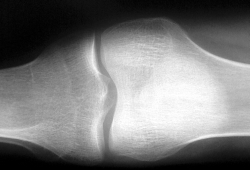

Reumatoidná artritída

Reumatoidná artritída (RA) je chronické zápalové ochorenie, ktoré sa prejavuje najmä postihnutím kĺbov, z toho pochádza aj jej názov artritída (arthritis – zápal kĺbu). Okrem kĺbov postihuje chorobný proces aj svaly a ich šľachy, väzy, teda najmä pohybové ústroje. Ochorenie však môže postihnúť aj iné orgány tela ako napr. kožu, oči, pľúca. Vlastná príčina choroby nie je doteraz známa, podstatou ochorenia je porucha imunitného systému, ktorý začne vnímať vlastné tkanivá ako cudzie, následkom čoho sa spustí zápalový proces.

Diagnózu možno stanoviť na základe podrobného vyšetrenia kĺbov, doplneného o laboratórne skúšky a röntgenové snímky. Pri prvých príznakoch choroby možno vysloviť len podozrenie na reumatoidnú artritídu, až ďalší vývoj ukáže či ide skutočne o túto chorobu. Nebezpečenstvo reumatoidnej artritídy spočíva v tom, že chorobný zápalový proces na kĺboch postupuje do hĺbky, zasahuje vždy ďalšie a ďalšie kĺby a zanecháva trvalé následky. Takto vznikajú deformácie kĺbov ako napr. ohnuté kolená, členky, zápästia, pritiahnuté ramená.